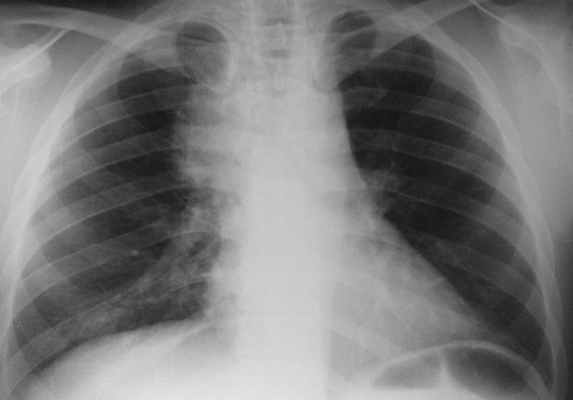

Обычная рентгенография грудной клетки в двух проекциях может выявить косвенные признаки медиастинита, такие как подкожная эмфизема, латеральное или переднее отклонение трахеи и наличие плеврального выпота.

Проводится тщательное рентгенологическое обследование (рентгенография грудной клетки, томография, рентгенография пищевода, пневмомедиастинография). Рентгенологически при медиастините может выявляться расширение тени шеи и средостения, эмфизема средостения, пневмоторакс, гидроторакс, уровень жидкости в средостении, пищеводные свищи.

- обзорная рентгеноскопия и –графия органов грудной клетки (обязательно в двух проекциях- передне-задней и боковой) – с ее помощью фиксируют эмфизему средостения (раздутие воздухом, попавшим сюда через дефекты тканей), а на более поздних этапах – признаки гноя;